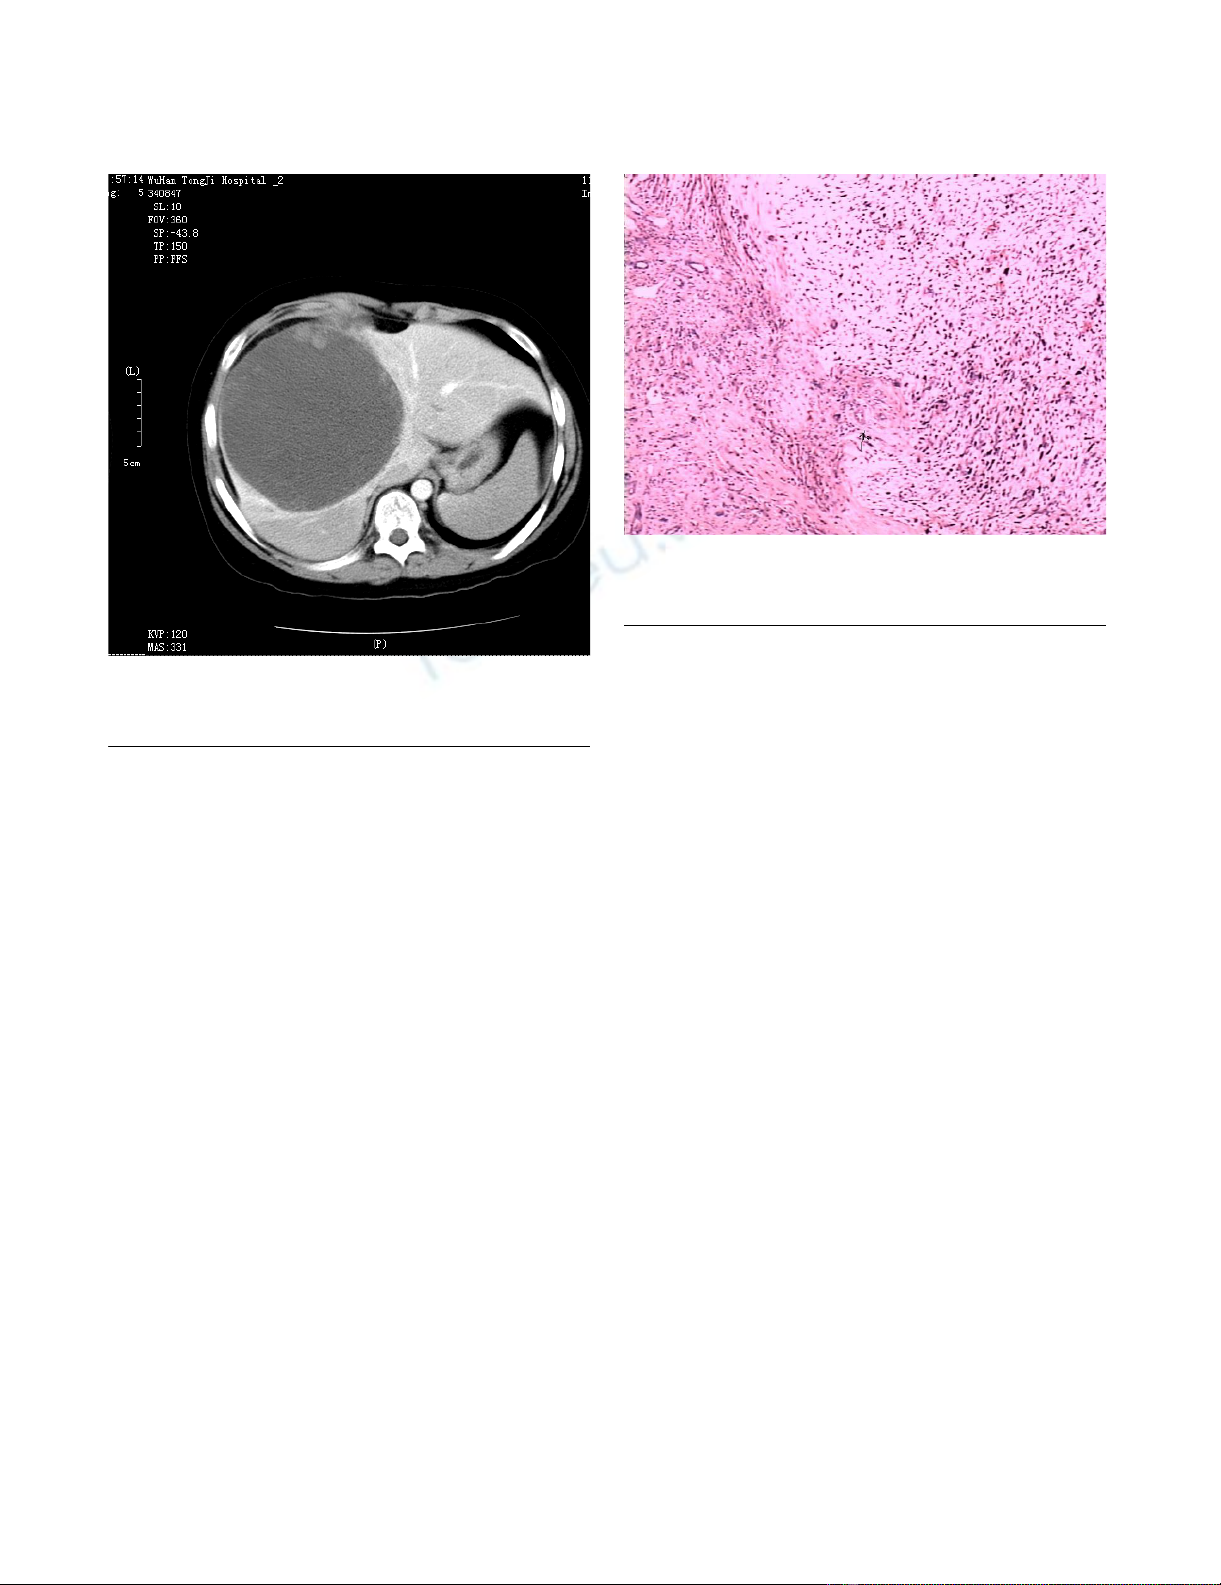

ment. Contrast enhanced CT Scan revealed a large,

hypodense mass of 14 × 15 × 15 cm in the right lobe of

the liver. (Figure 1). Exploratory laparotomy was per-

Contrast enhanced CT scan showing hepatomegaly and a large hypodense lesion in the liverFigure 1

Contrast enhanced CT scan showing hepatomegaly and a

large hypodense lesion in the liver.